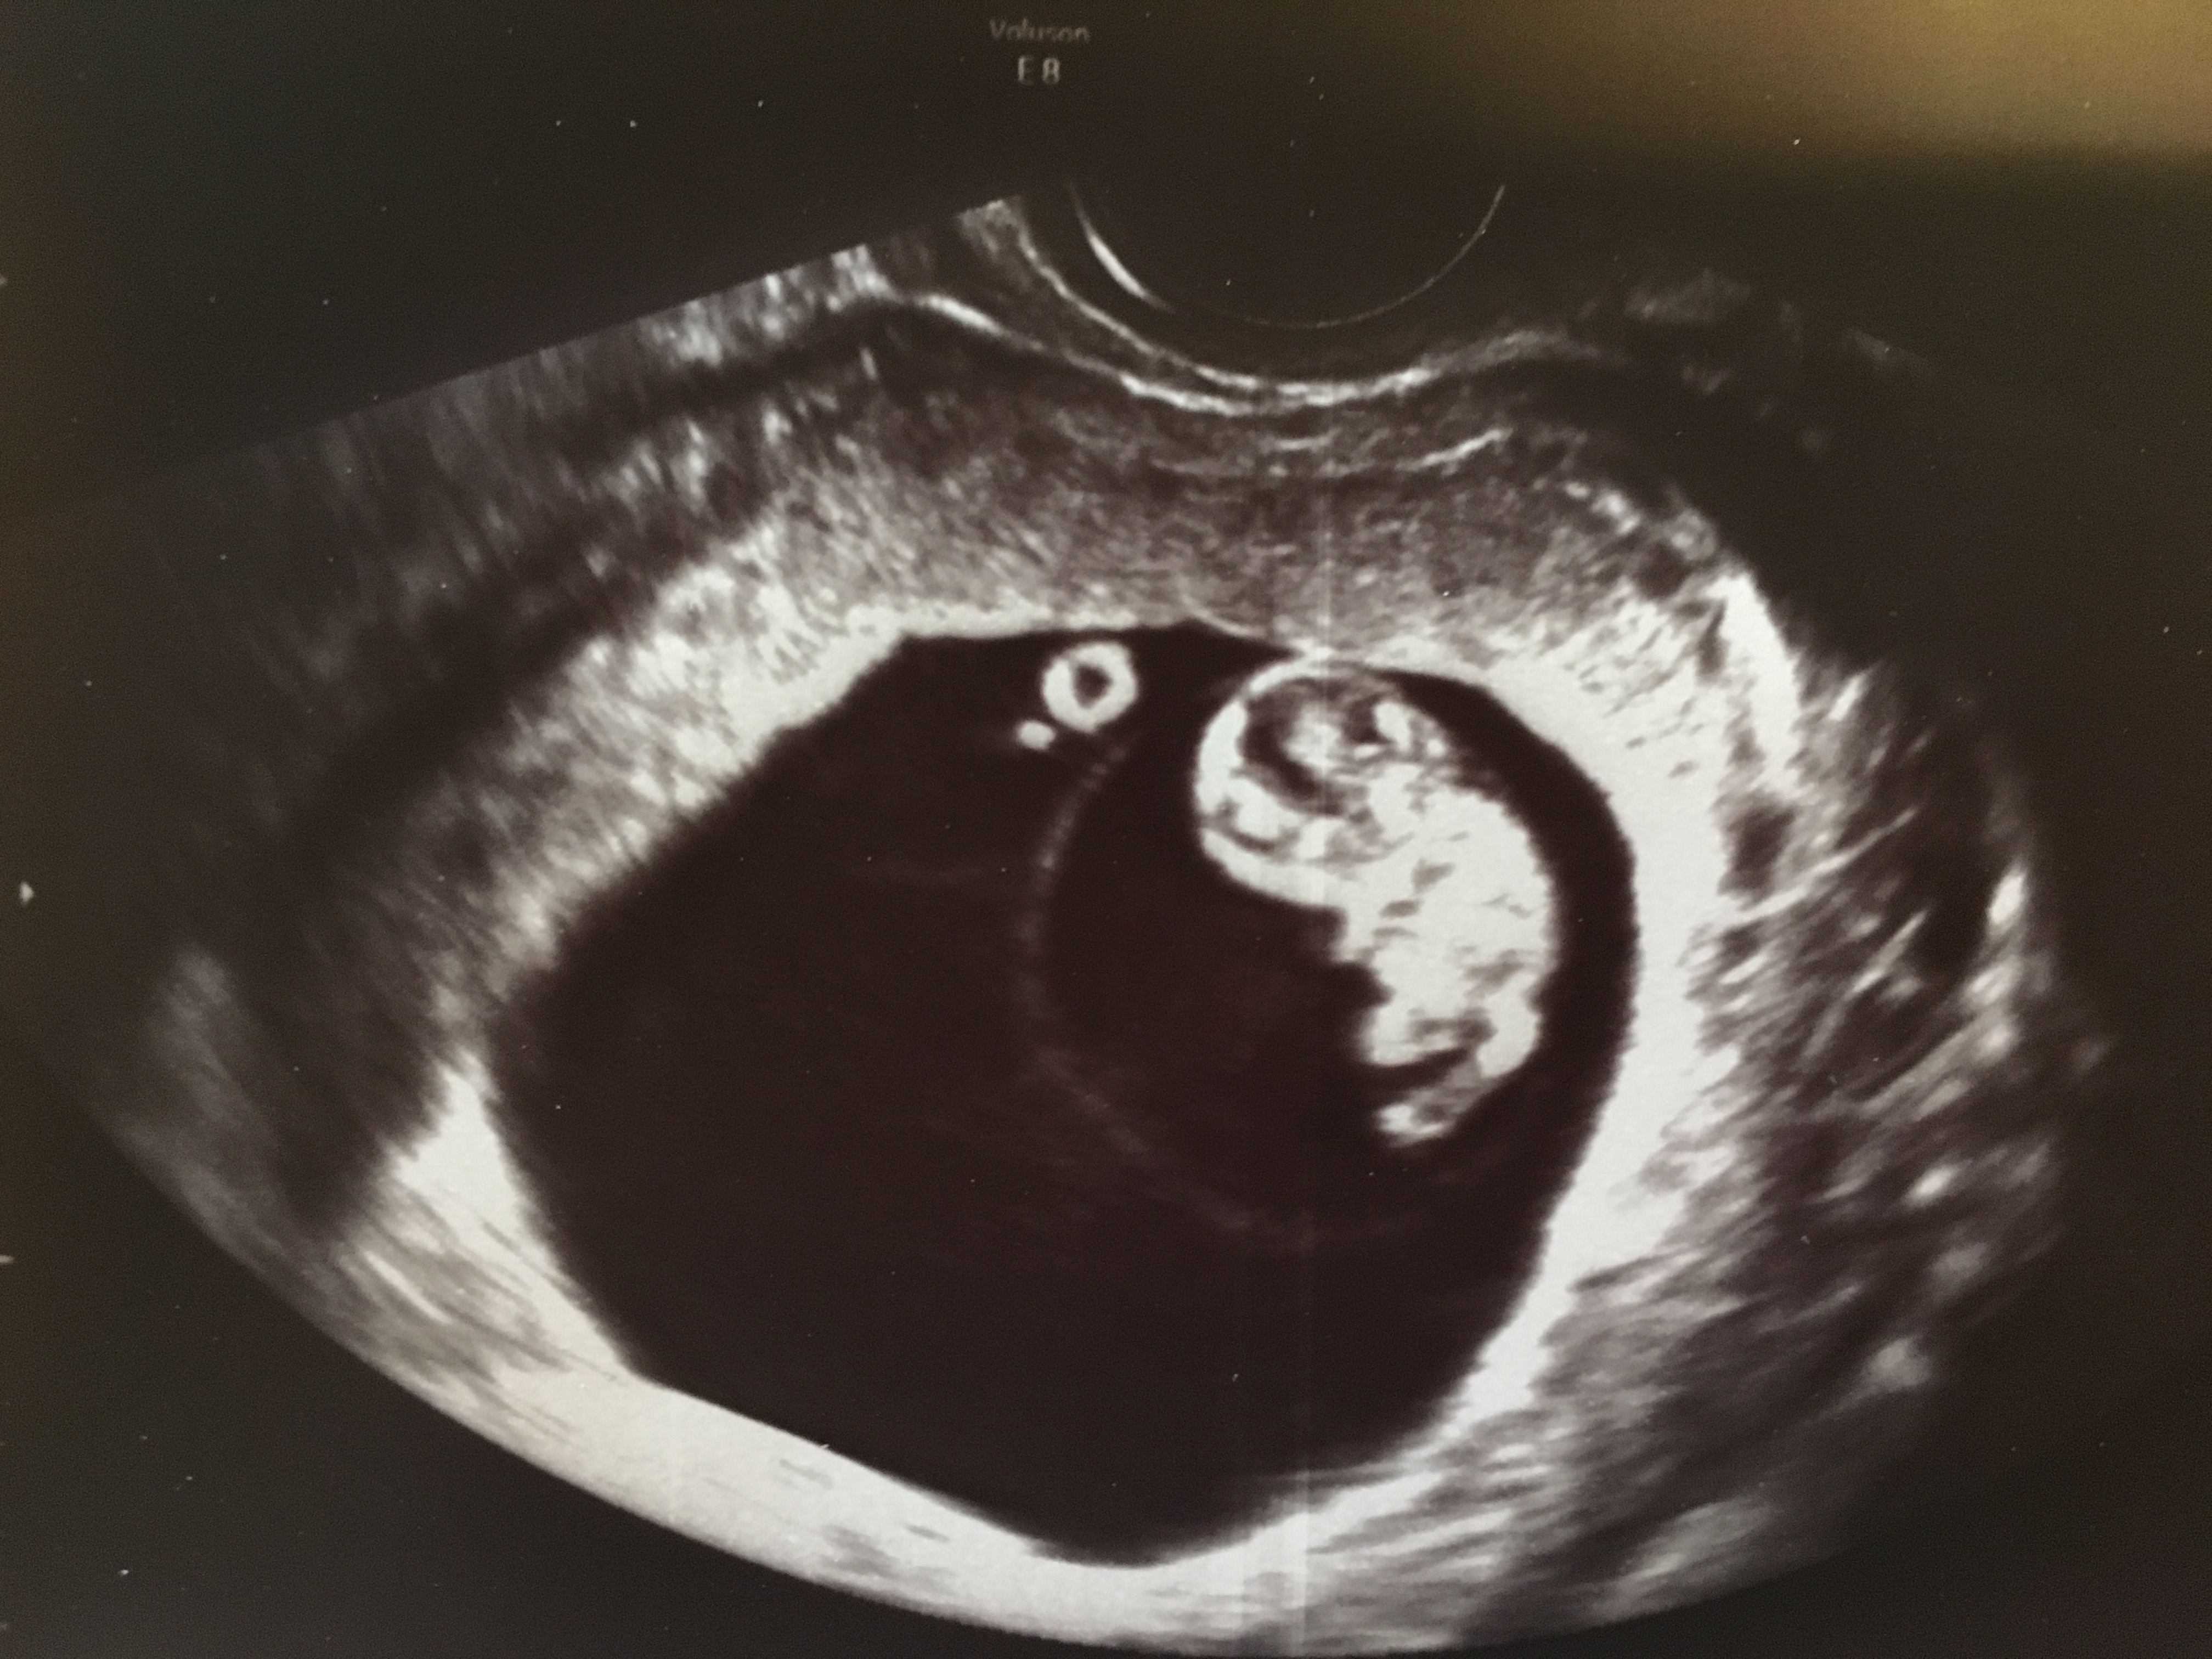

Twins!!!!!! I had two ultrasounds, one week apart.